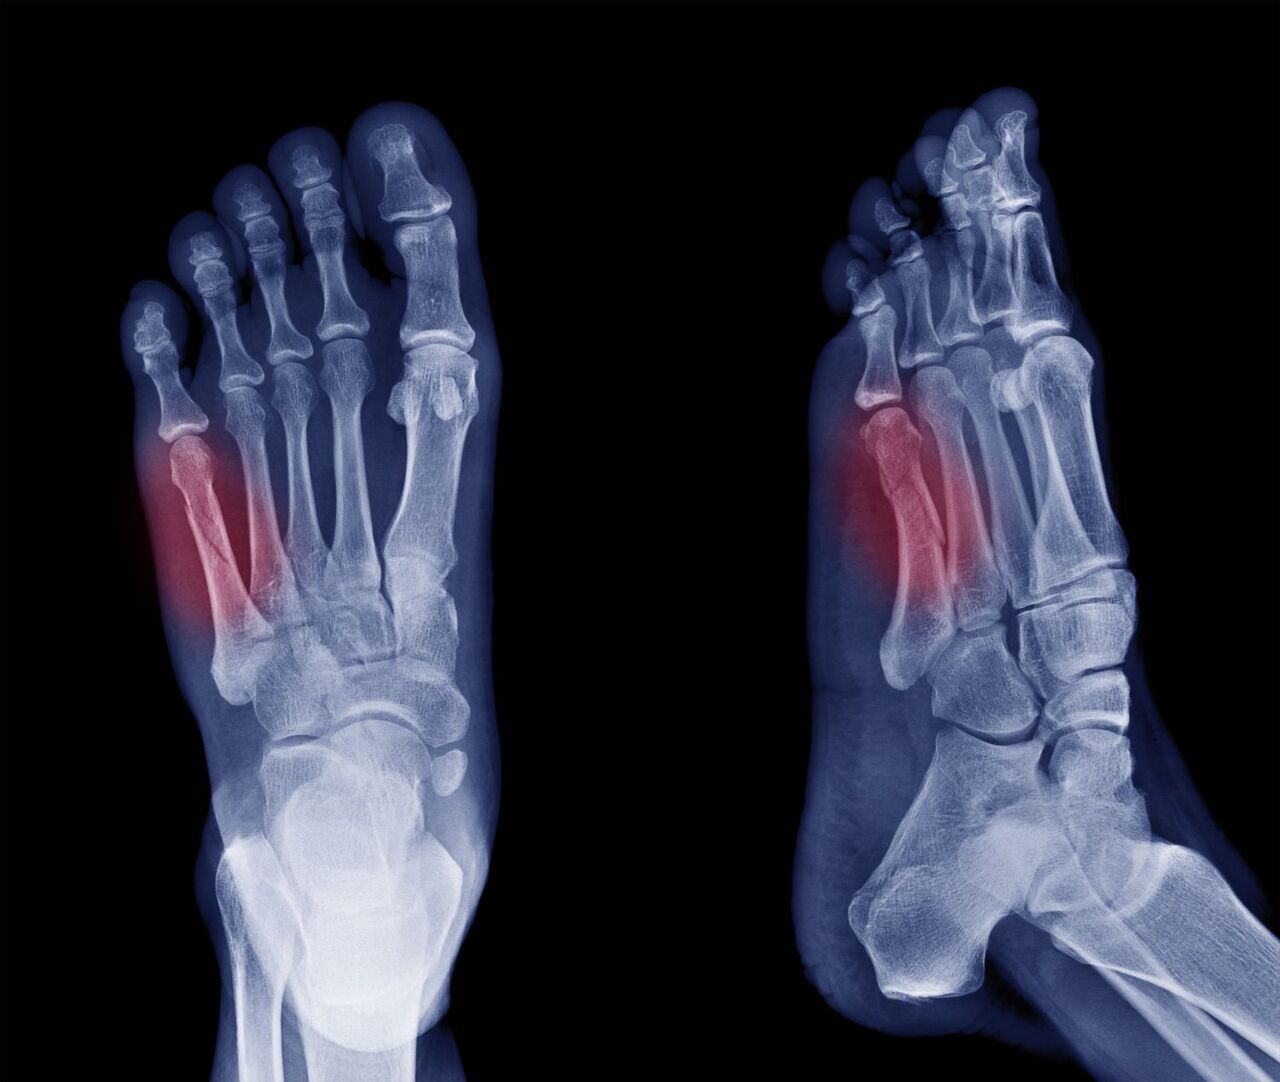

발가락 골절의 원인 및 증상

발가락 골절 역시 여러 원인으로 인해 발생할 수 있으며, 그중 가장 흔한 원인은 무거운 물체가 발가락에 떨어지는 경우입니다. 운동 중 부상, 실족하여 발가락이 끼이는 사고, 혹은 신발이 맞지 않아 발생하는 골절도 있습니다.

발가락 골절의 증상으로는 발가락 부위의 심한 통증, 부기, 멍, 발가락의 변형, 걷기 어려움 등이 있습니다. 또한, 골절된 부위를 움직일 때 통증이 더욱 심해질 수 있습니다.